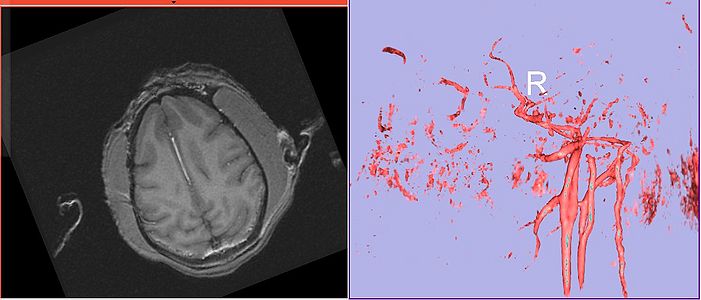

Angio sequence (right name?) has apparently been used for some (7 out of 10) subjects CLW: This is normal T1w blood flow artifact, but it is pronounced, perhaps because of the small brain size.